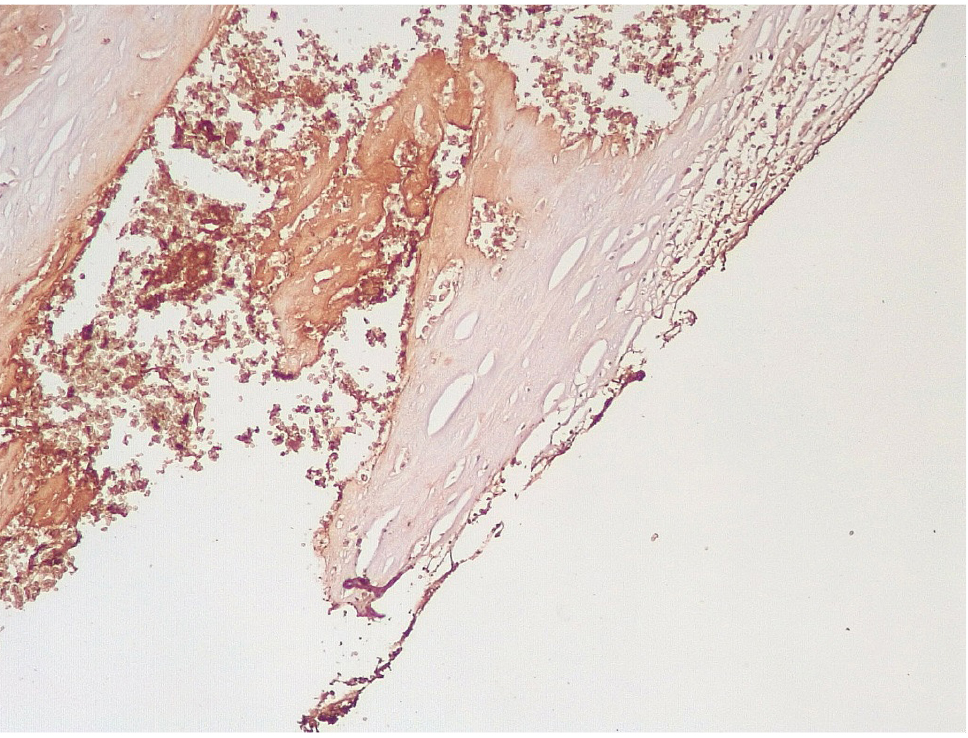

Сохранялась резковыраженная яркая экспрессия ФВ как со стороны интимы, так и субинтимально, в участках альтерации атером (рис. 8). В то же время экспрессия белка CD31 была негативной на всем протяжении стенок КА.

Рис. 8. Яркая экспрессия ФВ в интиме и субинтимально в местах разрушения атером КА. Иммуногистохимическое исследование с антителами к vWF. Ув. ×200